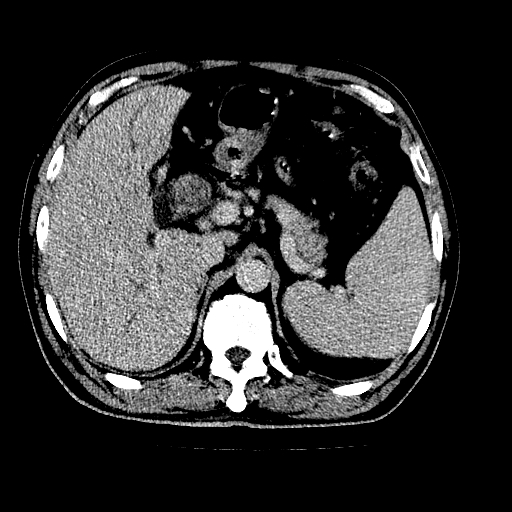

男,66岁,上腹部不适、黄染一周。彩超示:肝左叶占位,肝内胆管扩张,胆总管扩张,胆总管占位?

肝左叶不规则软组织肿块影,边缘不规整邻近肝实质受累分界不清;肝内胆管(左叶)明显扩张成“软藤状”,诊断:肝左叶胆管细胞癌。

肝左叶占位性病变,并胆管扩张,符合胆管细胞癌ct表现,门脉左支受累,左肾囊肿。窗宽太窄了,其他的看不清

左叶胆管细胞癌累及胆总管,门脉左支受侵,慢性胆囊炎胆结石,左肾小囊肿

支持肝左叶肝内胆管细胞癌伴胆总管及门脉左支受侵。